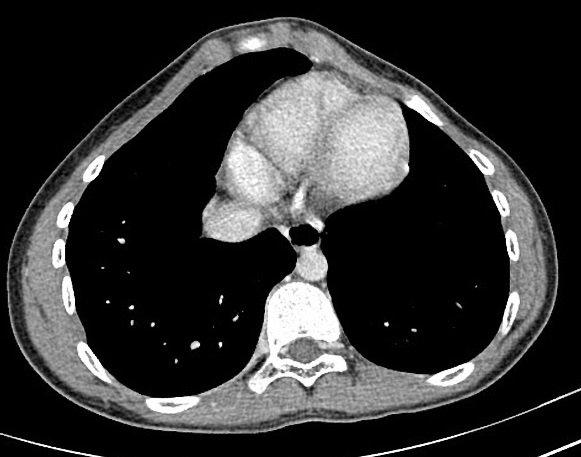

Syndrome pariétal avec lésion osseuse de hypodense

1/3 posterieure du cote droit (métastase

costale).

Image radiologique

TDM en coupe axiale |

Image radiologique TDM d'une tumeur

parietal à origine costale ( metastase costale ) |